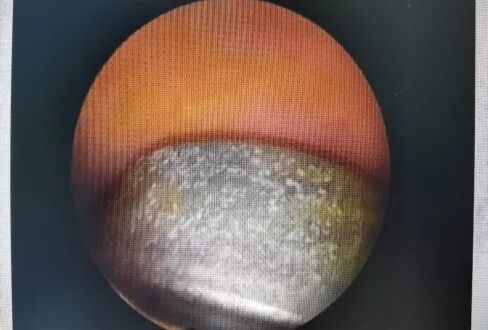

術中見

取出異物

術畢見

孩子媽媽聽到要手術取出異物后,手足無措,連忙問道:“大夫,手術會對孩子的陰道和處女膜有損害嗎,會影響到她以后的生活嗎?”。安撫孩子及其母親、充分溝通后,婦科團隊為患者在靜脈全麻下行了無損傷處女膜宮腔鏡檢+陰道內異物取出,僅僅數(shù)分鐘,就從小女孩陰道內順利取出一直徑約1.0cm圓餅狀空心金屬玩具、高約0.5cm,再次鏡檢證實異物已取凈,陰道粘膜無損傷,沒有對小孩造成任何傷害。